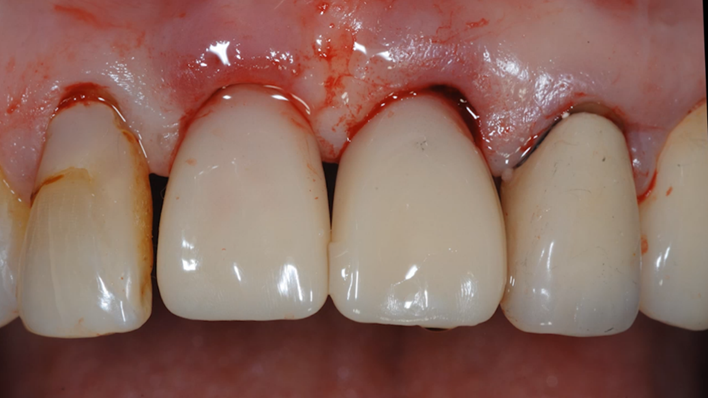

Clinical case: Extraction, immediate placement & loading using

R2GATE solution in aesthetic zone

- Courtesy of Dr. Jong-Cheol Kim, Korea-

Clinical case: : R2GATE guided surgery & immediate implant placement

- Courtesy of Dr. Kwang Bum Park, Korea -